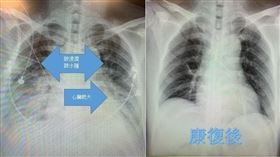

小感冒一週後竟胸悶氣喘成「心肌炎」

一名49歲男性,以為是一般感冒到他院去看診,一個多禮...